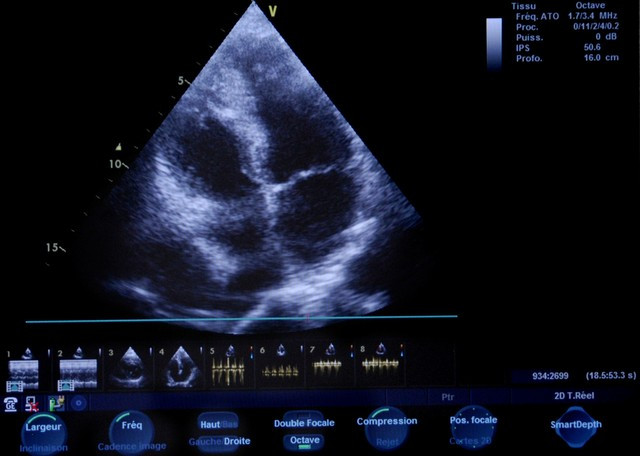

第一个检查:心脏超声

低压,医学上叫舒张压,它反映的是心脏舒张时,血管里的最低压力。低压高,很多时候和心脏功能、血管弹性脱不了干系。

比如有些患者,因为长期熬夜、压力大、爱生气,导致心率偏快,心脏舒张的时间变短,血管里的血液来不及回流,压力自然就降不下来;还有些人是因为心肌肥厚,心脏泵血的 “泵体” 出了问题,也会让低压居高不下。

做心脏超声,能清楚看到心肌的厚度、心室的大小、心脏的收缩和舒张功能,还能排查有没有心室肥厚、瓣膜反流这些问题。早发现,就能早干预,避免小问题拖成心肌缺血、心衰的大麻烦。

我之前有个 40 岁的患者,低压常年 95 左右,总说胸口发闷,一开始没当回事,后来做心脏超声发现心肌已经轻度肥厚了。赶紧调整生活方式,配合中药调理,半年后低压降到 85,复查心脏超声,心肌厚度也恢复了正常。